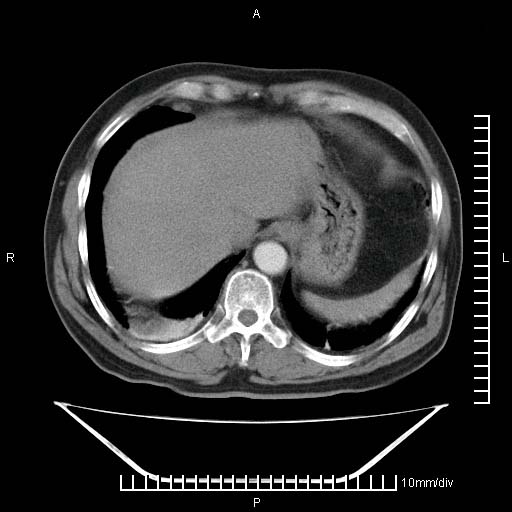

标题: CT25082:肝脏增强:男性,70岁 [打印本页]

标题: CT25082:肝脏增强:男性,70岁

患者以心脏疾病收住院,腹部无明显症状,b超查肝脏有占位。

增强效果不理想。考虑转移,胆囊壁明显增厚,不排除胆囊癌肝转移。

牛眼征,中心坏死无强化,外缘强化,最外缘又见低密度,考虑转移,与脓肿鉴别

1)肝脏多发性转移瘤(不排除胰尾癌转移所致可能)。2)腹水。3)右侧少量胸腔积液。

ct25082 结果:转移瘤

外院mr结果:胰尾恶性占位。